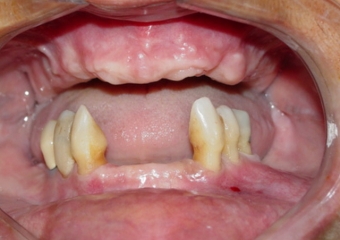

Imagem inicial

Imagem dos Implantes Superiores Instalados